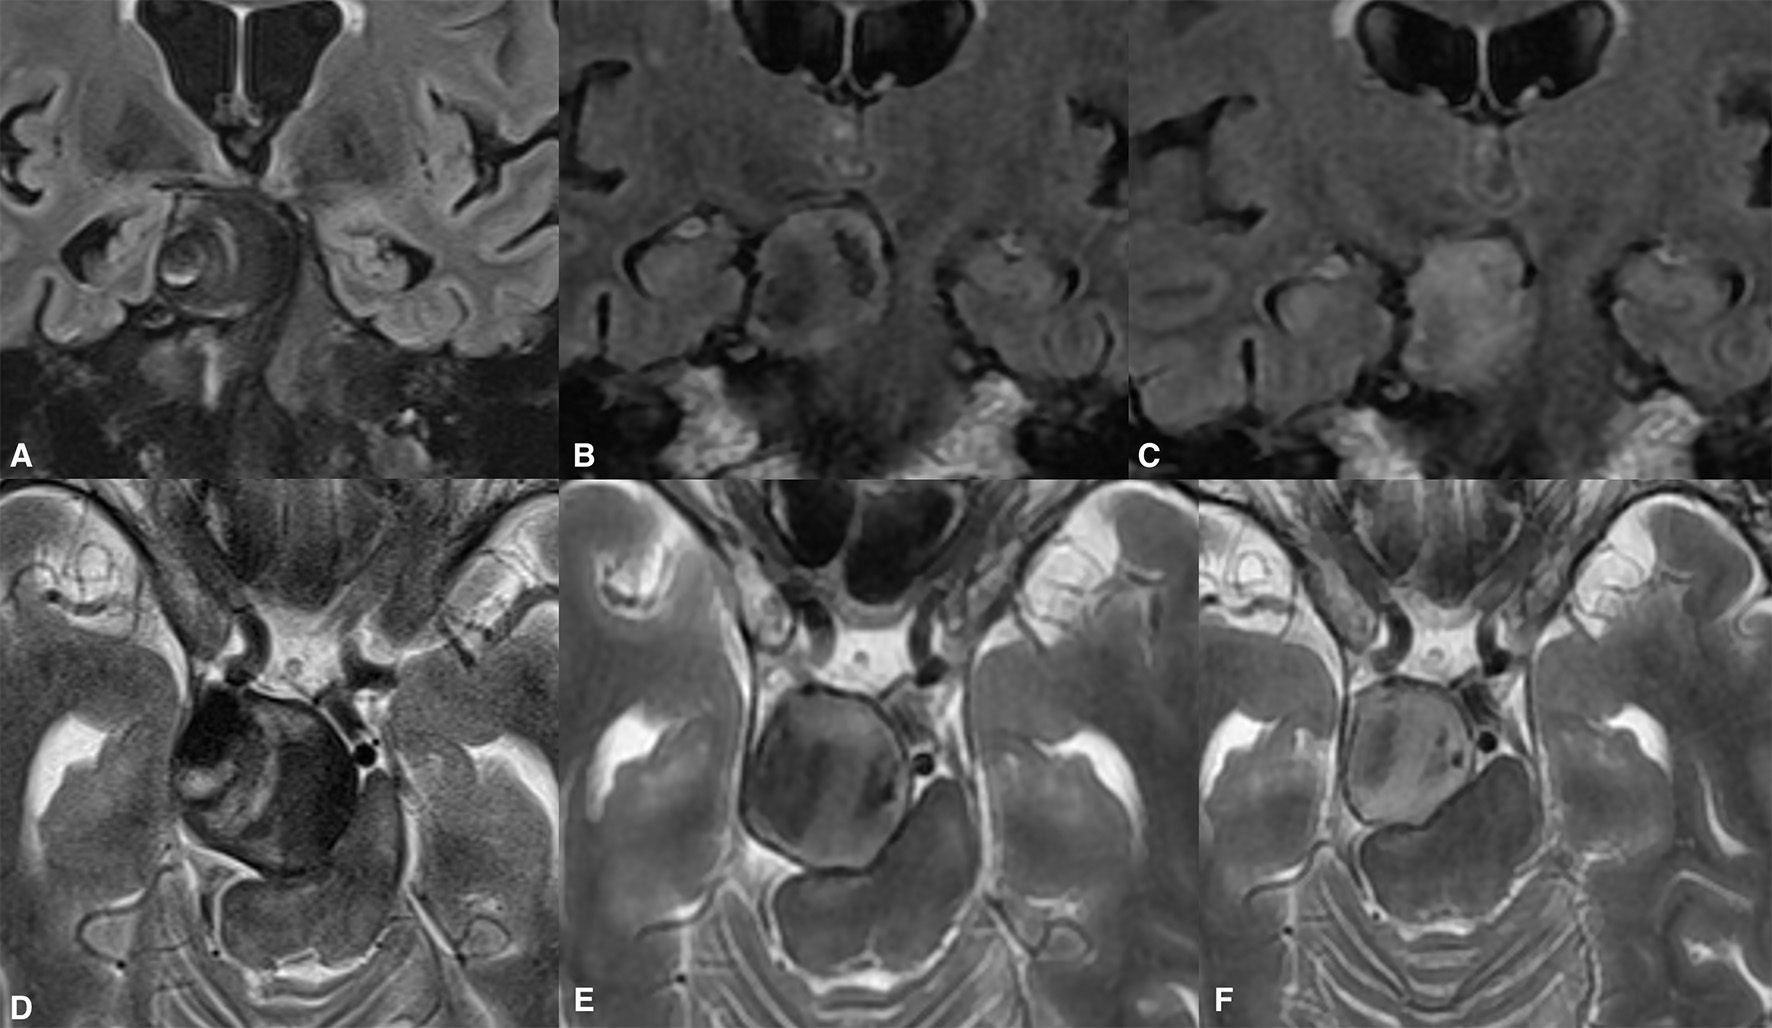

Figure 4

Giant extradural ICA (A) aneurysm demonstrating significant shrinkage following flow diversion. Despite the complete thrombosis of the aneurysm found on the first radiological follow-up, there were neglectable changes in the aneurysmal volume (B). One year post-treatment, the aneurysm shrinkage was visible on the MRI (C). The complete resolution of the aneurysm-induced compression of the left temporal lobe and the significantly diminished volume were present on long-term follow-up [(D), arrow].